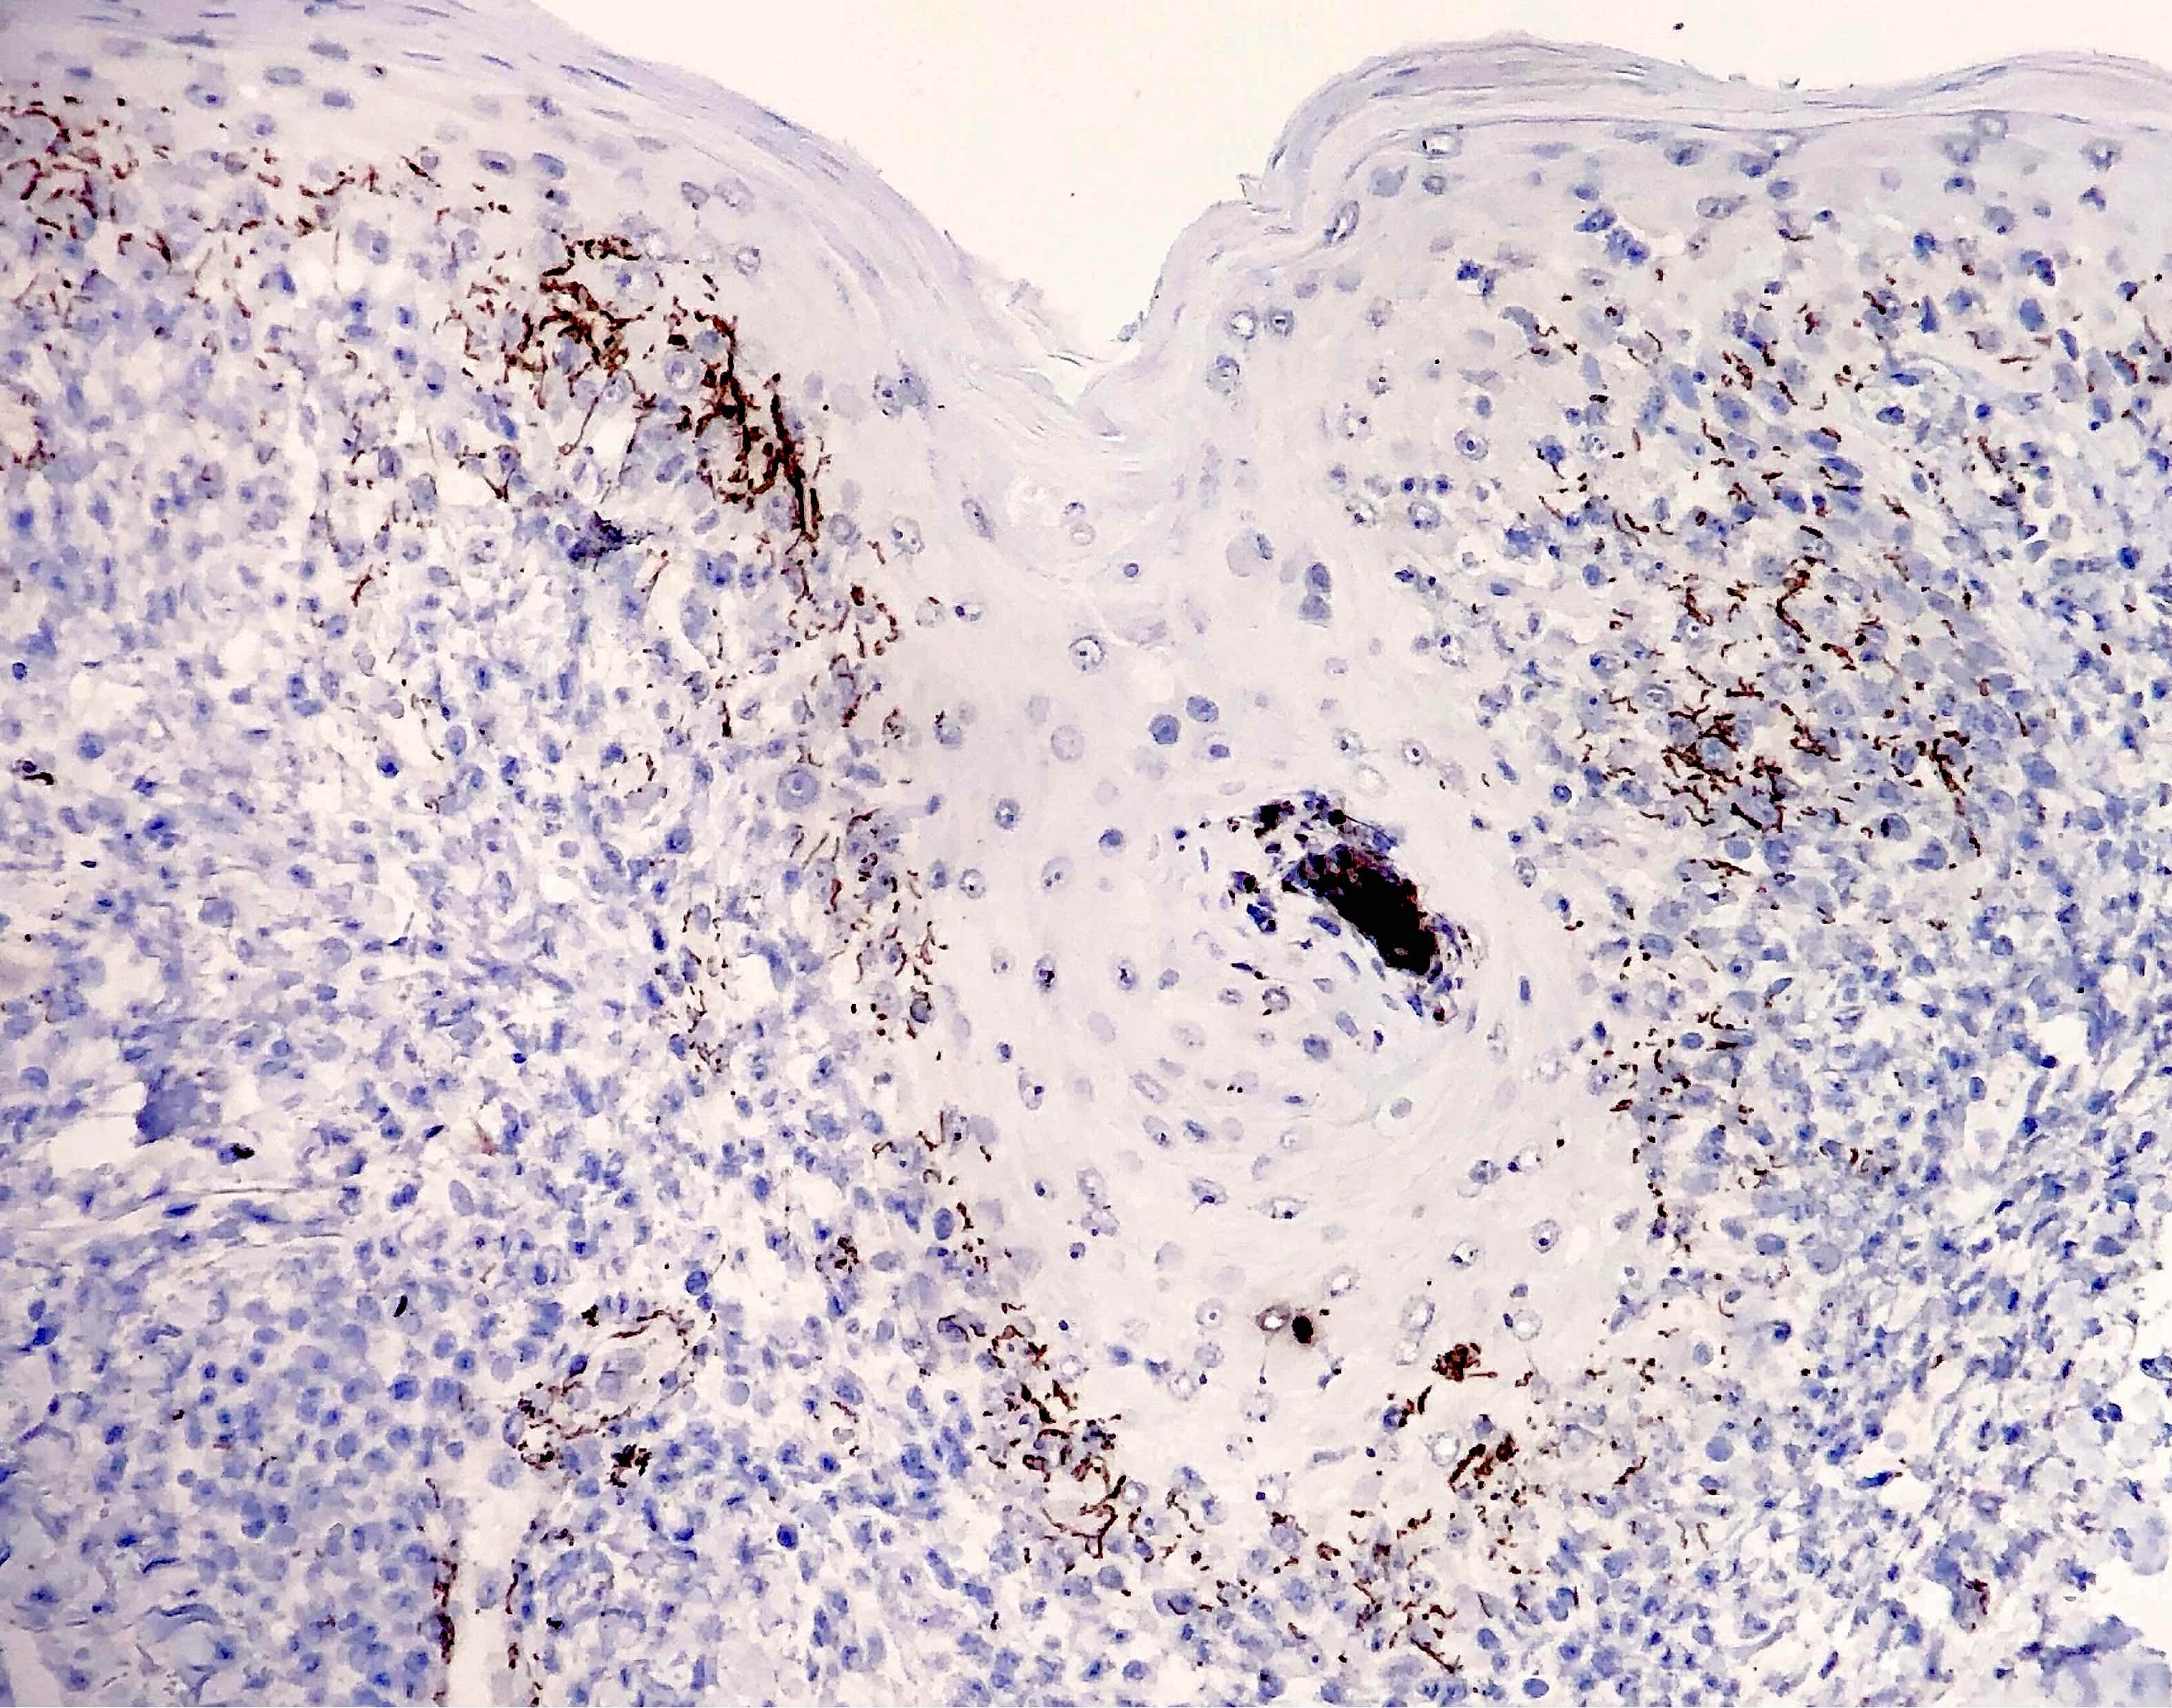

Microscopic (histologic) images

Contributed by Silvija P. Gottesman, M.D., Hillary Rose Elwood, M.D., Mark R. Wick, M.D. and AFIP images

Positive stains

- Silver stains: Warthin-Starry or Steiner stain (41% sensitive) (J Cutan Pathol 2004;31:595)

- Immunohistochemical stain: treponema (71% sensitive) (J Cutan Pathol 2004;31:595)

- Comment: There is psoriasiform epidermal hyperplasia with superficial and deep perivascular lymphohistiocytic infiltrate. Admixed plasma cells are also noted. The infiltrate forms a band beneath the hyperplastic epidermis and envelopes some of the adnexal structures. Endothelial swelling of the superficial vascular plexus is present. A treponemal immunohistochemical stain shows numerous coiled spirochetes in the lower half of the epidermis. These findings are diagnostic of syphilis.

- Secondary syphilis:

- Lichenoid superficial and deep perivascular and periadnexal lymphohistiocytic inflammation with admixed plasma cells

- Plasma cells may be absent in 33% of biopsies

- Marked endothelial swelling and proliferation of blood vessels can be seen

- Commonly identified are vacuolar interface change, acanthosis or lymphocyte exocytosis